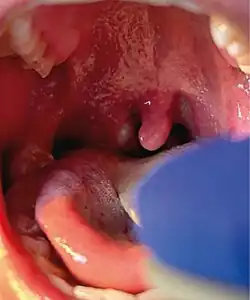

The rash comprises numerous small lesions, which may appear on the palms, soles, face, mouth, throat, genitals, or anus.[1] They begin as small flat spots, before developing into small bumps, which then fill with fluid, eventually bursting and scabbing over, typically lasting around ten days.[2] In rare cases, lesions may become necrotic, requiring debridement and taking longer to heal.[26][24]